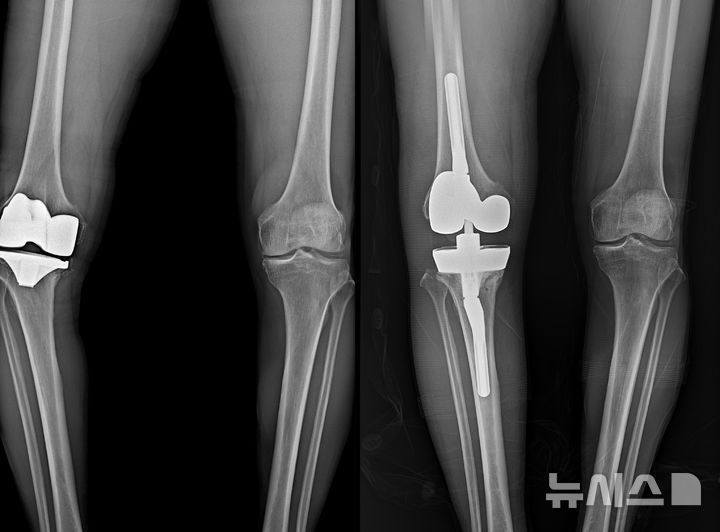

보건복지부 지정 관절전문 연세사랑병원은 최근 무릎 인공관절 재치환술 1000례를 달성했다고 밝혔다. 이 가운데 최근 10년 동안만 833례가 집계됐다. 무릎 인공관절의 내구성은 현재 평균 20년 정도로 평가되며, 과거 10년에서 15년 수준이던 수명이 꾸준히 길어지고 있다. 병원 측은 제3세대 인공관절 디자인, 네비게이션 수술, 로봇 수술, 인공지능 기반 3차원 수술 시뮬레이션, 맞춤형 수술도구 등 디지털 기술이 도입되면서 수술 정렬 정확도와 삽입물 위치 정밀도가 향상된 결과라고 설명한다.

무릎 인공관절은 대개 일정 기간 사용 후 마모가 발생하지만, 고령화로 인한 사용 기간 증가뿐 아니라 초기 수술에서의 부정정렬, 인공관절 불안정성, 삽입물 해리, 감염 등으로 재수술이 필요해지는 경우도 적지 않다. 국내외 연구들에서는 전체 인공관절 수술의 5퍼센트에서 10퍼센트 정도가 재치환 대상이 되는 것으로 보고되고 있다. 수요층 확대와 함께 재수술의 의료적 난이도와 비용 부담이 의료 시스템 전반에 부담 요인으로 거론돼 왔다.

연세사랑병원 인공관절재수술센터는 누적 1000례 경험을 기반으로 표준화된 재수술 프로토콜을 구축해 수술 안정성과 효율성을 높이고 있다고 설명한다. 정형외과, 내과, 영상의학과, 통증의학과가 참여하는 협진 시스템을 전면 가동해 정확한 원인 진단, 환자 상태에 맞춘 수술 전략, 수술 후 통증 관리와 재활까지를 하나의 경로로 설계하는 방식이다. 특히 AI 기반 3차원 시뮬레이션과 로봇 수술 장비를 활용해 수술 전 삽입물 위치와 절삭 범위를 가상 환경에서 반복 검증하고, 실제 수술에서는 로봇과 내비게이션을 통해 계획된 각도와 깊이를 그대로 구현하도록 지원한다.

이 같은 디지털 수술 계획과 다학제 협진 체계를 통해 재수술 시간도 단축되고 있다. 보통 인공관절 재수술은 첫 수술 대비 두 배 이상 시간이 걸리는 고난도 수술로 인식돼 왔다. 그러나 연세사랑병원 재수술센터의 최근 평균 수술 시간은 1시간 10분에서 20분 수준으로, 첫 수술 평균 40분에서 50분에 비해 약 30분 정도만 더 소요되는 것으로 집계됐다. 수술 시간이 줄어들면 마취 유지 시간과 출혈, 감염 위험 등을 상대적으로 낮출 수 있어 고령 환자에게 유리하다는 평가가 나온다.